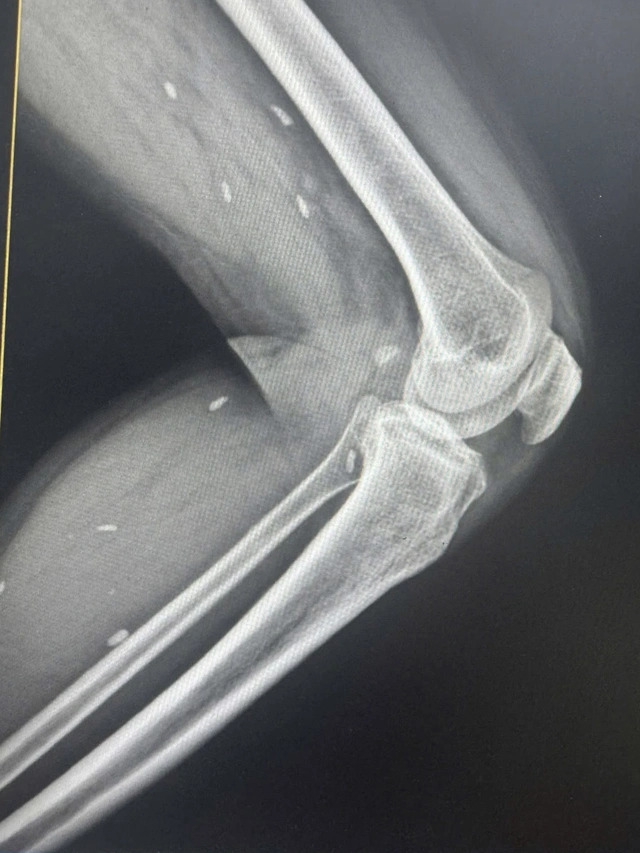

Theo đó, người bệnh đến thăm khám khi có triệu chứng mệt mỏi, đau nhức nhiều ở vùng chân, lưng, hạn chế vận động… Bệnh nhân được chỉ định thực hiện chụp X- quang thường quy.

Bác sĩ Đỗ Hồng Thanh, Phó Giám đốc Trung tâm Y tế khu vực Thạch Hãn cho biết, kết quả X – quang phát hiện nhiều kén sán kích thước như hạt gạo nằm rải rác ở các mô vùng xương đùi và cẳng chân bệnh nhân.

| Chụp X- quang, bác sĩ phát hiện các mô vùng xương đùi và cẳng chân bệnh nhân có nhiều kén sán kích thước như hạt gạo |

Theo lời kể của bệnh nhân cho biết có thói quen ăn rau sống. Bệnh nhân được chuyển lên tuyến trên điều trị với chẩn đoán nhiễm kén sán.